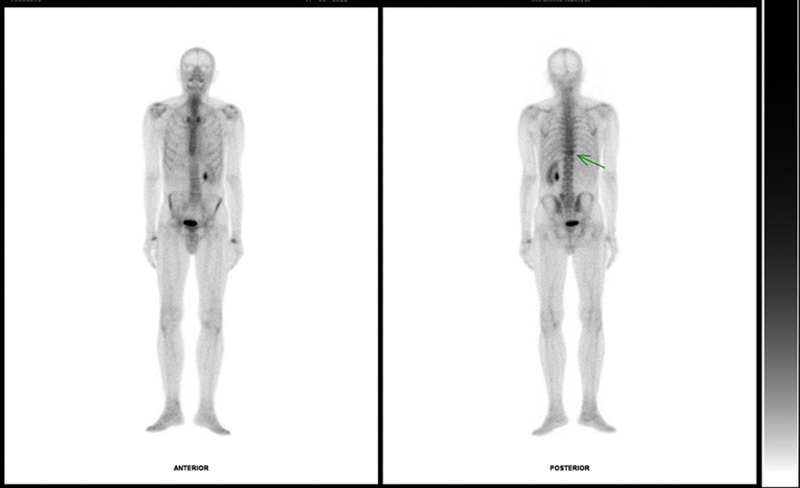

Collisions lesions are rare neoplasms where two histologically distinct tumors coexist in the same organ or anatomical site. Vertebral hemangiomas (VHs) are the most common lesions involving the vertebral bodies and imaging findings of typical and atypical hemangiomas, variant forms of hemangioma such as aggressive hemangiomas are well known, but collision lesions involving VHs are extremely rare. This article presents a case report of a 73-year-old male patient diagnosed with clear cell renal cancer in a rare presentation of a bone metastasis coinciding with the same anatomical position as a VH (collision lesion). This required a multidisciplinary approach involving various diagnostic techniques to determine the best therapeutic management.